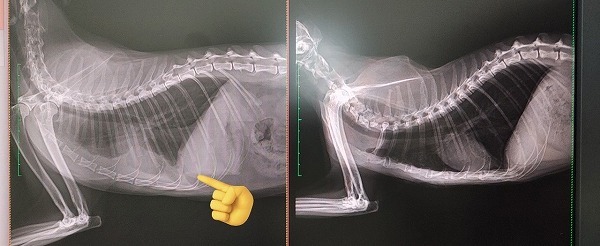

かかりつけ医にて受診しました。40.3度の発熱が有り、採血をします。SAA(血清アミロイドA蛋白)150以上の為、胸部レントゲンを行い胸水を認めます。胸水を検査に提出し、ネコインターフェロンを皮下注射し帰宅。この時点でほぼFIPで確定と診断されます。帰宅後すぐにFIPについて調べ、FIPの治療を専門的に行っている病院を見つけ、問い合わせました。『らんま』は、胸水を抜いたからか少し動けるようになりました。

右が正常な状態です(通常SAAは0.0~6.0だそうです)

FIP治療を専門的に行っている病院に受診中、かかりつけ医からFIP陽性の連絡が入りました。再度、採血・レントゲン・新たにエコー検査を行います。胸水の明らかな増悪なく、入院は不要と判断されました。お薬が処方され、内服開始します。